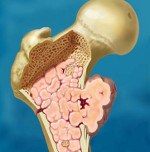

Первичный рак костей - рак, начинающийся в кости . Чаще поражает детей и подростков. Нередко передается по наследству. Пол, образ жизни значения не имеют.

Это редкое заболевание. Причина не известна, но часто прослеживается роль генетических факторов. Чаще всего опухоль появляется в костях ног, выше или ниже колена.